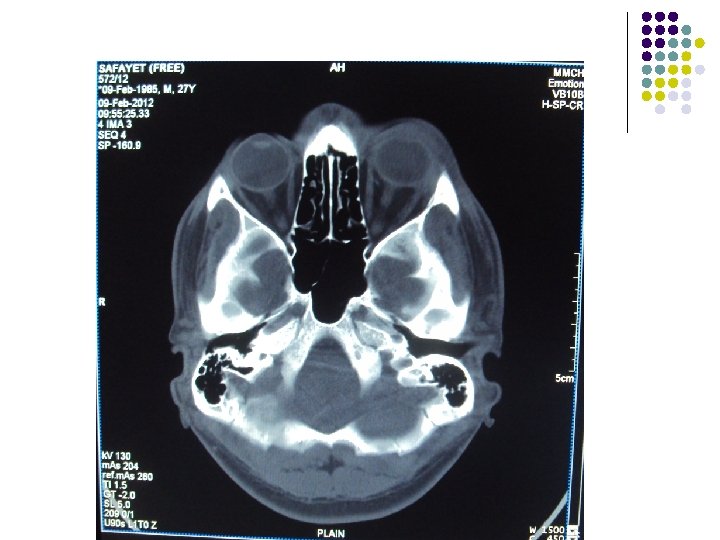

CT Scan of Brain

Clinical Diagnosis Retrobulbar solid tumour on left orbit